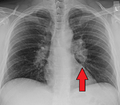

Hilar adenopathy especially on the person's left (AP CXR)

Hilar adenopathy especially on the person's left (lateral CXR)

Hilar adenopathy especially on the person's left (coronal CT)

Hilar adenopathy especially on the person's left (transverse CT)